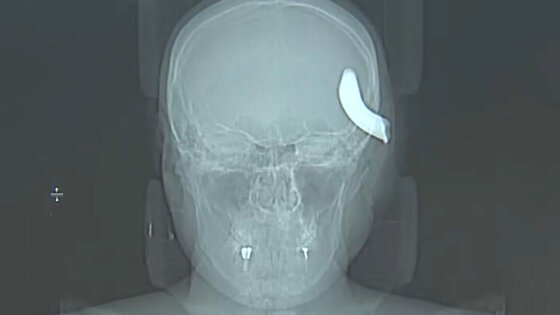

В Петербурге нейрохирурги извлекли из черепа молодого мужчины металлический крюк от буксировочного троса

Несчастный случай произошел в Приморском районе в апреле, когда мужчина решил помочь другу с буксировкой автомобиля. Когда машину тянули, зацепив тросом, крюк на нем размером 6х4 см не выдержал, оторвался и с силой отлетел прямо в голову Никиты. Так, с металлическим крюком в голове, пострадавшего и доставили во второе нейрохирургическое отделение больницы.

Хирурги в экстренном порядке отправили пострадавшего на операционный стол, провели ему декомпрессивную трепанацию черепа и удалили металлический фрагмент. Операция длилась три часа.